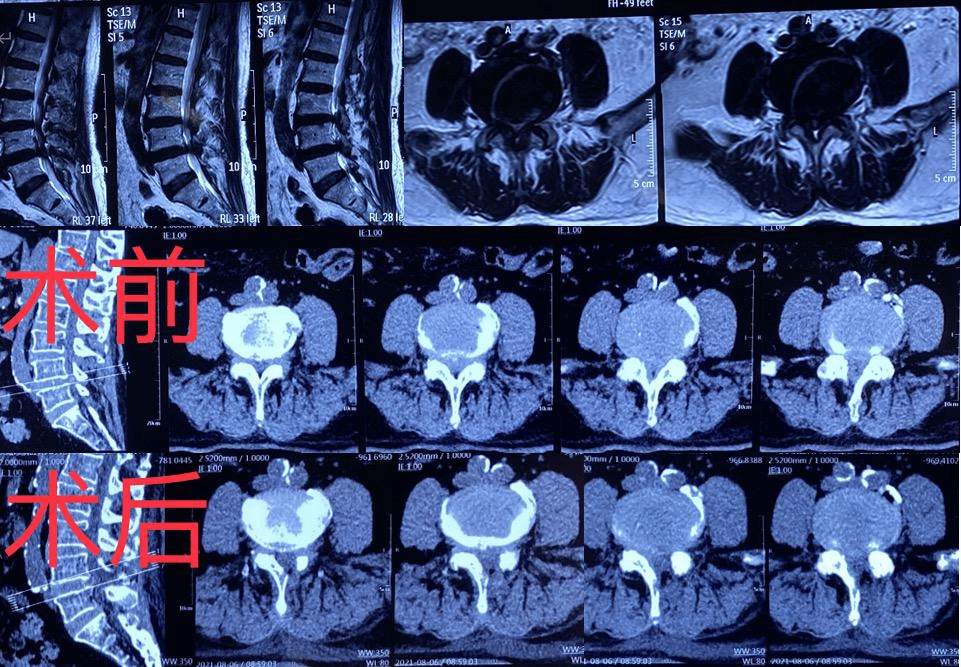

周先生在家人陪伴下,到哈医大一院群力院区骨科就诊,王岩松经过影像学等相关检查确诊为“腰椎间盘突出症、腰椎管狭窄症”。由于周先生的超高龄且合并高血压、心脏病、脑梗、呼吸系统等基础疾病,手术与全身麻醉风险极高,王岩松团队经过心内科、呼吸内科、神经内科、麻醉科等多学科会诊讨论,完善相关术前检查后,王岩松教授、王义文主治医师在局麻监护下成功为其进行经皮椎间孔镜微创手术,手术共耗时40分钟,出血5ml,仅需缝合1针,术后下肢疼痛、麻木等症状明显缓解,症状恢复良好,术后2天顺利出院。